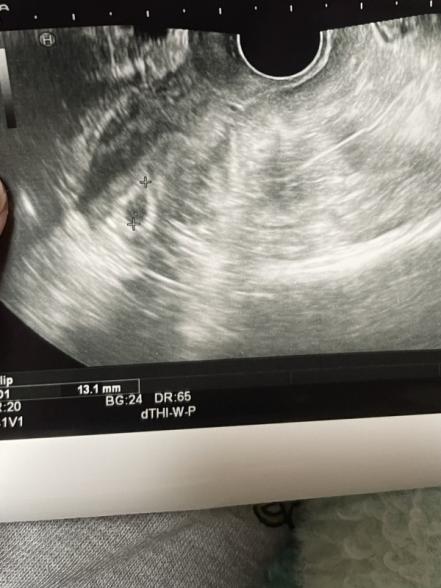

胎嚢の中に白の線が見える感じがするのですが気のせいでしょうか?

胎嚢の中に白い線が見える感じがすると書かれていたのですが、お写真を拝見する限りではよくわかりませんでした。

また5週かと思っておられたところ、4週相当だということだったのですね。

実際の胎嚢の大きさなどわからないのですが、排卵の時期にずれがあったのか、思っておられるよりも週数が浅くなっていたのかなと思いました。